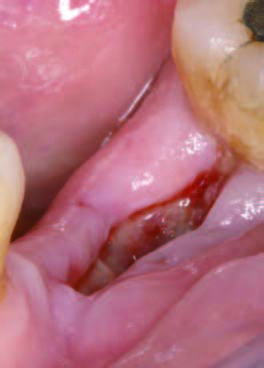

15日後歯肉の状態

一方、自然治癒の場合、穴が完全に塞がるまでに数ヶ月かかることがあります。その間に、ドライソケット(抜歯窩治癒不全)を引き起こしたり、食べ物が詰まることで痛みや悪臭が発生することもあります。